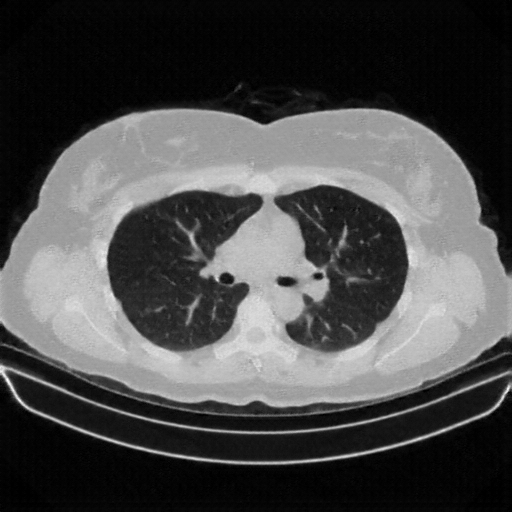

Generated VENOUS CT scan (A→B translation)

Full window (WL 1023.5, WW 4095 β†’ Low βˆ’1024, High +3071)

Lung window (WL -600, WW 1500 β†’ Low βˆ’1350, High +150)

Mediastinum window (WL 40, WW 400 β†’ Low βˆ’160, High +240)